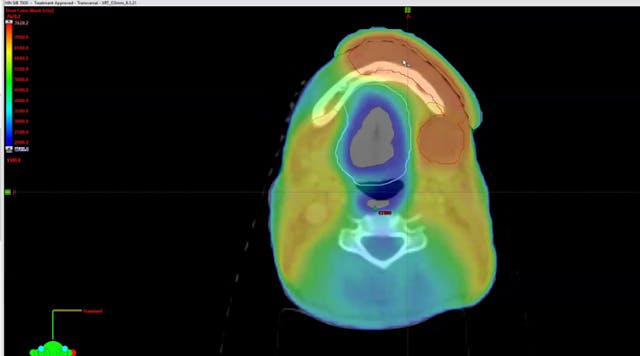

02/26/2024 - Dr. David Sher - Radiation Oncology - Head & Neck

lymph nodes, tonsillectomy, multiple biopsies, HPV positive, NavDx, neck dissection, probability of primary emergence, lingual tonsillectomy, ipsilateral node, right node, toxicity levels, avoid the larynx, base of tongue, skin cancer, balding, postauricular lymph node, biopsy, squamous cell carcinoma, rapid onset, CT scan, PET scan, MRI scan, perineural invasion, carotid, bolus printing, bolus shell, p16 unknown primary, level 1B lymph node, HPV negative,